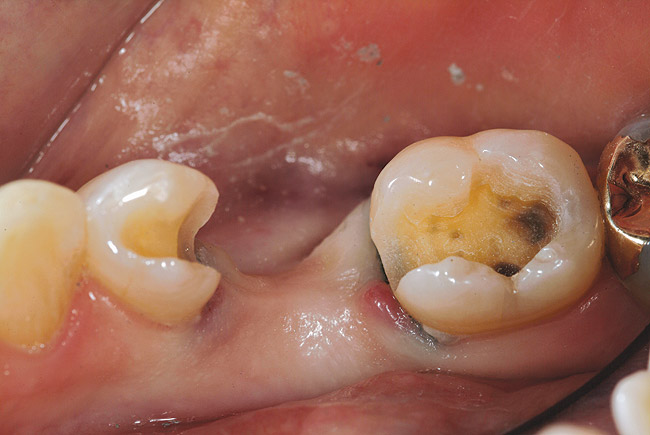

Figure 6a  Missing mandibular premolar; the patient has declined the placement and restoration of missing tooth with an implant. The clinical decision was for a fiber FPD.

Figure 6a

Figure 6b  Sizing instrument to prepare the proximal box to an adequate width for the Tescera quartz fiber U-Beam.

Figure 6b

Figure 6c  Inlay preparations of abutment teeth for a FPD.